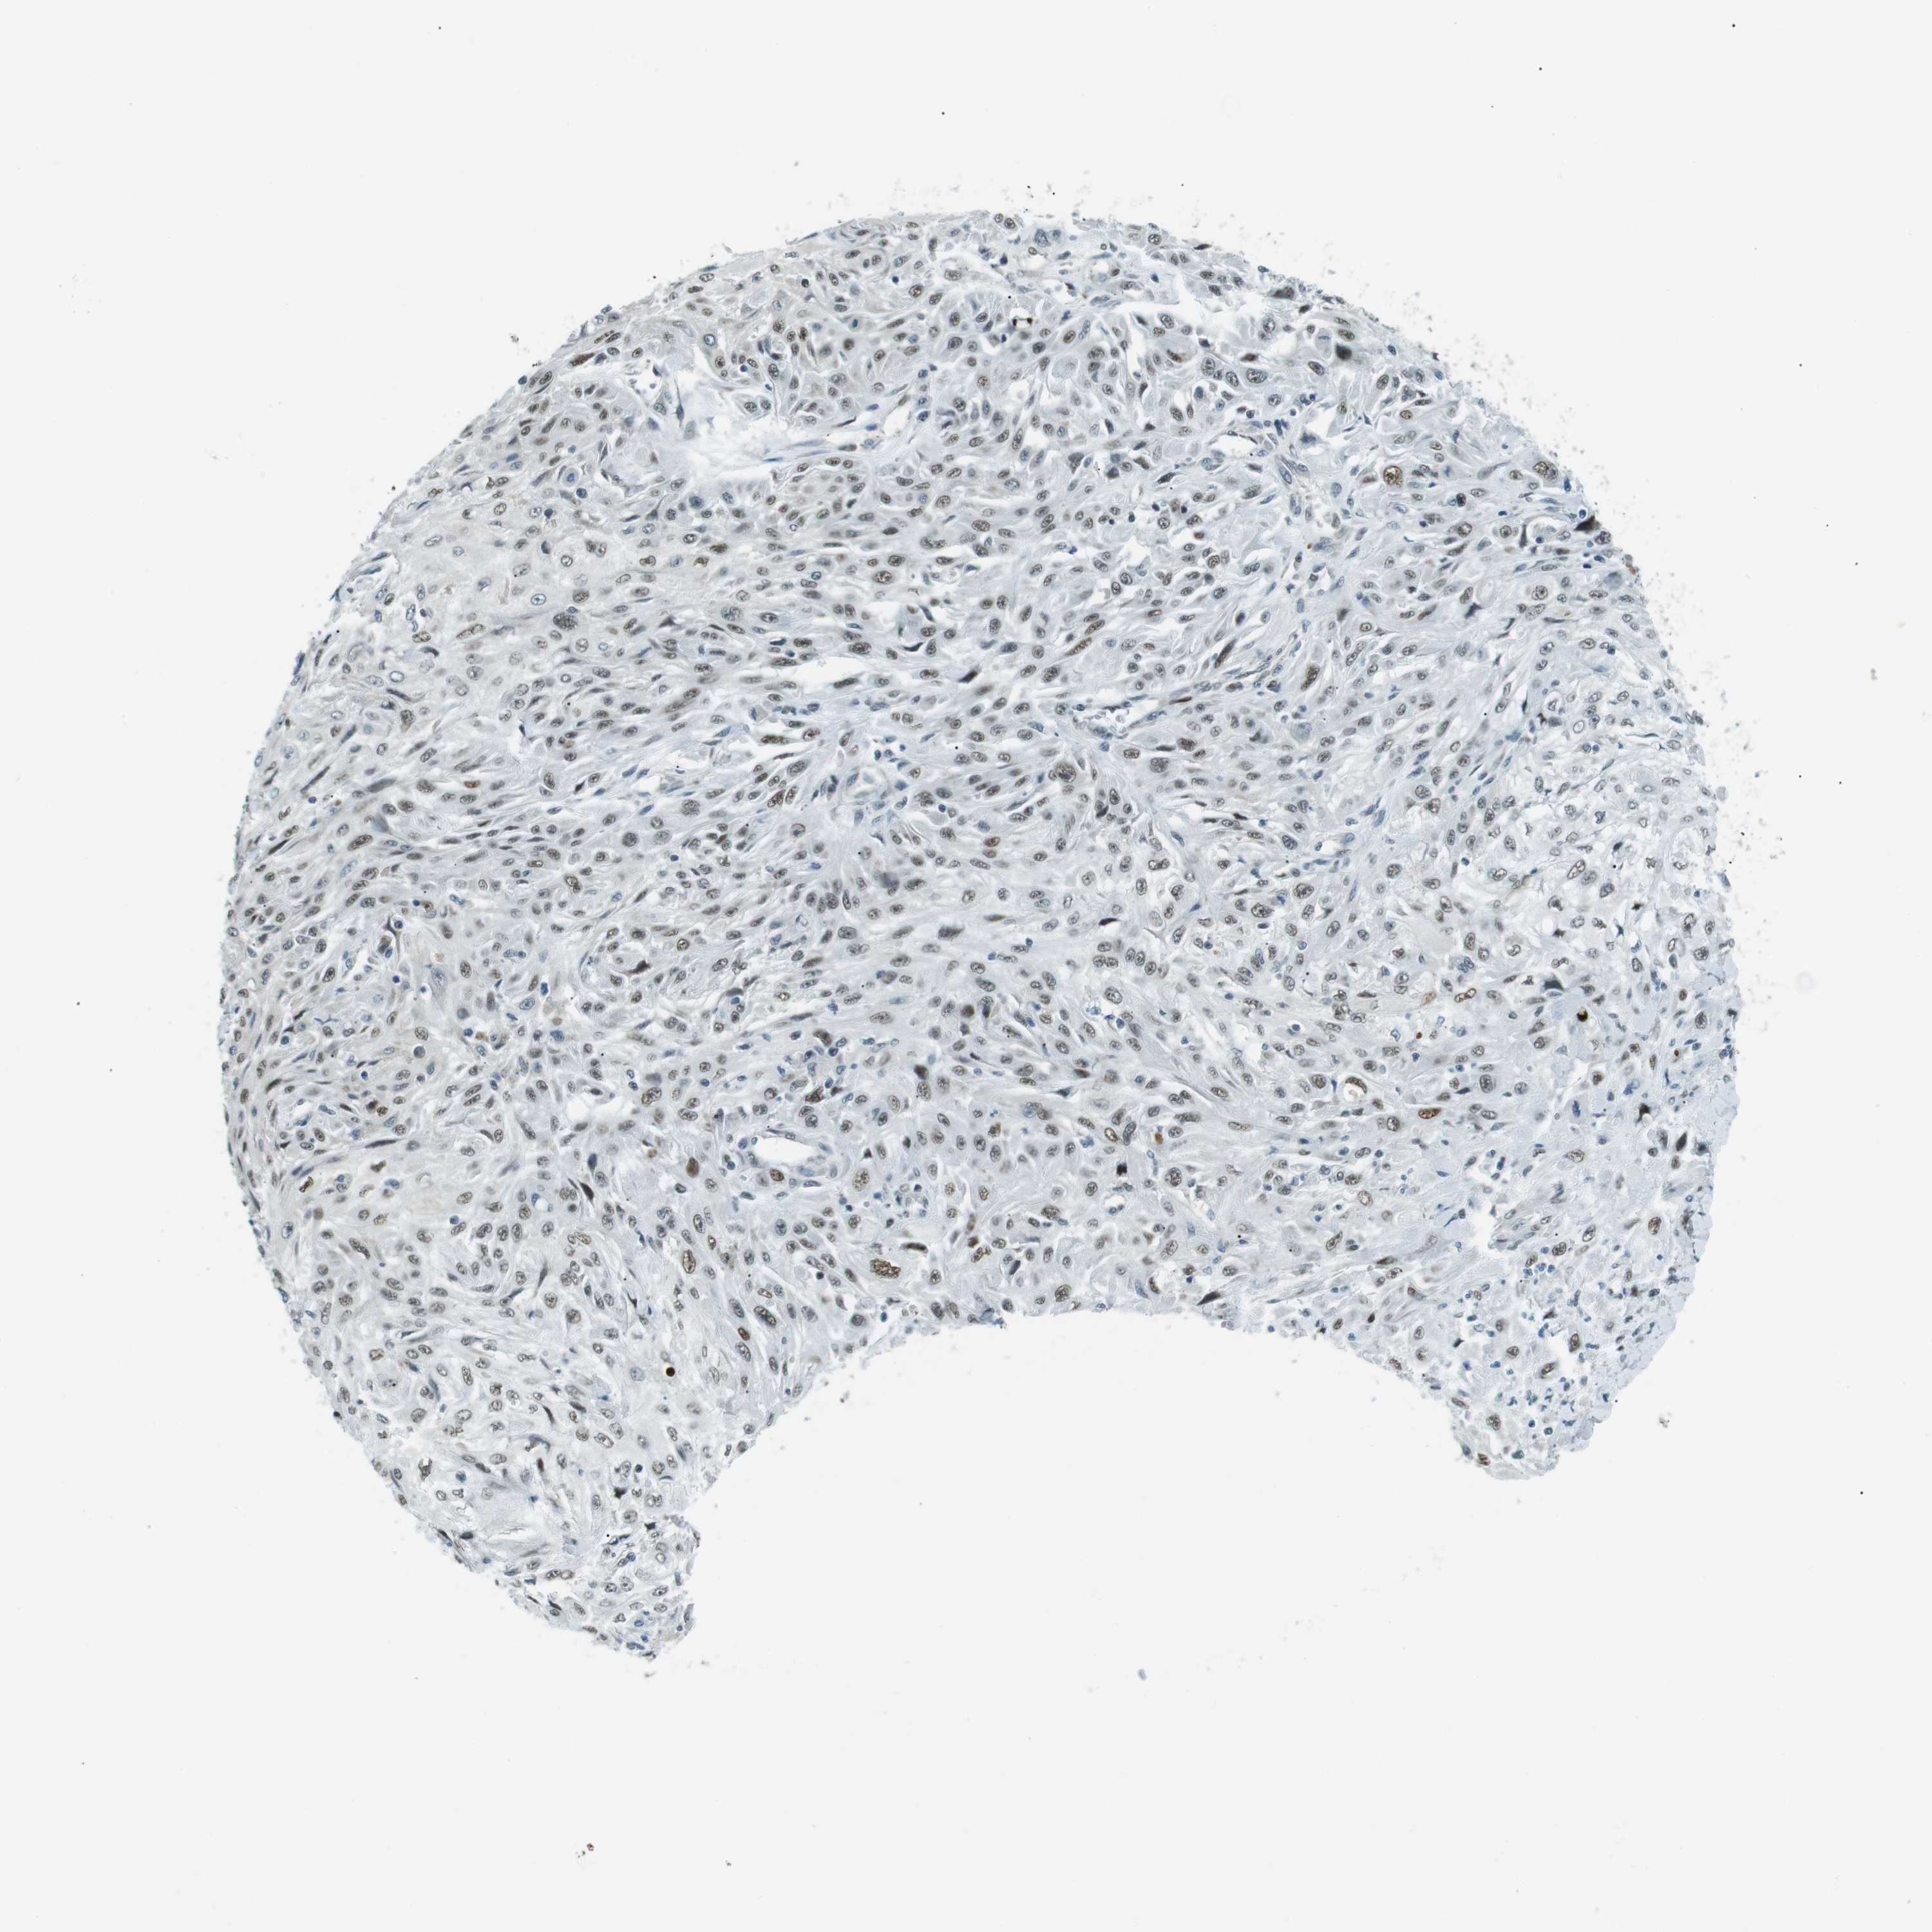

CANCER SKIN CANCER Show tissue menu

SKIN CANCER - Protein expressioni

A mouse-over function shows sample information and annotation data. Click on an image to view it in a full screen mode. Samples can be filtered based on level of antibody staining by selecting one or several of the following categories: high, medium, low and not detected. The assay and annotation is described here.

Each image is clickable and will lead to virtual microscopy that enables deeper exploration of all samples and also displays staining intensity scores, fraction scores and subcellular localization as well as patient and tissue information for each sample.

Antibody HPA000595

Staining

High

Medium

Low

Not detected

Intensity

Strong

Moderate

Weak

Negative

Quantity

>75%

75%-25%

<25%

None

Location

Nuclear

Cytoplasmic/membranous

Cytoplasmic/membranous,nuclear

Squamous cell carcinoma in situ, NOS

Squamous cell carcinoma, NOS

Basal cell carcinoma

Adnexal tumor, benign